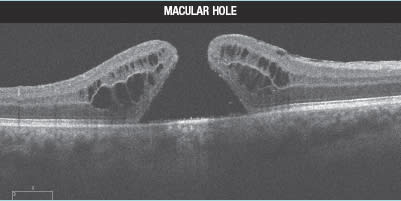

A 61-year-old woman is evaluated for gradually decreasing vision in her right eye for the past several months. Her visual acuity is 20/100, and she has central distortion and scotoma on Amsler grid testing. On clinical examination, there appears to be a macular hole with a cuff of retinal fluid. Imaging with the Cirrus SD-OCT in 5-line raster mode (Figure 1) shows a full-thickness break in the retina, with continuity between the vitreous and the RPE. There is cystic-appearing intraretinal fluid, and the retina has a typical rolled edge appearance. Although material within the retinal hole appears slightly more reflective than the vitreous, the bright reflectivity of the retinal pigment epithelium (RPE) and underlying choroidal structures confirms the absence of intact retinal tissue anteriorly. This patient does, indeed, have a full-thickness macular hole. She underwent pars plana vitrectomy with intravitreal gas and face-down positioning.